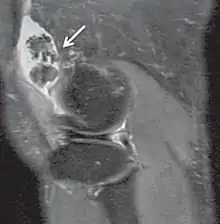

| Inversion recovery | Short tau inversion recovery | STIR | Fat suppression by setting an inversion time where the signal of fat is zero.[13] | High signal in edema, such as in more severe stress fracture.[14] Shin splints pictured: | ![]() |

Proton density

Proton density (PD)- weighted images are created by having a long repetition time (TR) and a short echo time (TE).[36] On images of the brain, this sequence has a more pronounced distinction between gray matter (bright) and white matter (darker gray), but with little contrast between brain and CSF.[36] It is very useful for the detection of joint disease and injury.[37]